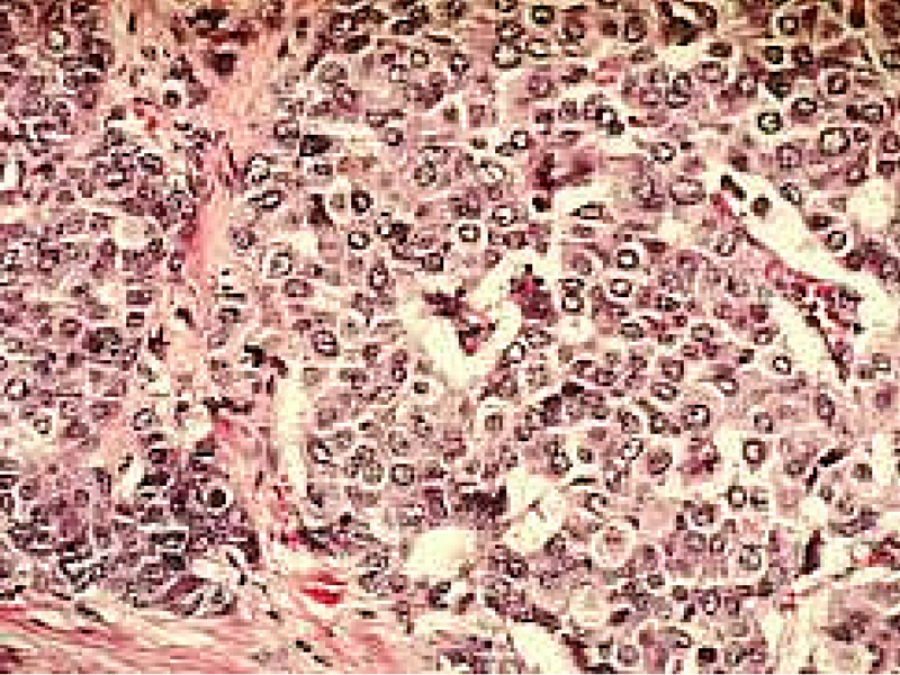

L'allarme sulla loro potenziale pericolosità è stato diffuso in quanto i risultati dello studio condotto dall'Università di Reading hanno evidenziato che dei 20 campioni prelevati da donne con tumore al seno ed esaminati, ben 18 presentavano elevate tracce di parabeni, in particolare metilparabeni. Inoltre in quattro dei venti campioni la concentrazione totale di parabeni era di circa due volte superiore ai valori medi ritrovati nelle venti pazienti. Il loro potere cancerogeno deriva, come affermato da questo studio, dalla capacità dei parabeni di comportarsi come gli estrogeni (Routledge et al., 1998, Byford et al., 2002; Darbre et al., 2002, 2003), ormoni che le donne producono naturalmente dalla pubertà alla menopausa e che, assunti in grande quantità, potrebbero facilitare la proliferazione delle cellule tumorali. In particolare i parabeni oltre che legarsi ai recettori degli estrogeni sono anche in grado di regolare l'espressione dei geni (es. pS2) che mediano l'attività estrogenica (Byford et al., 2002).Il possibile legame tra l'utilizzo dei deodoranti e l'insorgenza di cancro al seno sembrerebbe, inoltre, riconducibile al fatto che i parabeni ritrovati nei campioni esaminati si presentano in forma esterea e non sotto forma di metaboliti, indicando che la loro penetrazione nell'organismo non è avvenuta per assunzione orale (Darbre et al., 2003, 2004). Inoltre poichè uno dei modi utilizzati dall'organismo per eliminare i prodotti tossici è la "traspirazione", i deodoranti impedendo, in parte questo fenomeno ridurrebbero l'eliminazione delle tossine attraverso le ascelle. Ciò provocherebbe, con il tempo, un loro accumulo a livello delle ghiandole linfatiche presenti sotto il braccio e quindi un primo passo verso la formazione di cellule cancerose (Darbre et al., 2003). Tutto ciò è anche confermato da osservazioni cliniche, pubblicate nell'arco di 10 anni, che mostrano che la maggior parte dei tumori si sviluppa a livello del margine superiore esterno del seno, cioè in corrispondenza della zona in cui viene maggiormente applicato il deodorante (Haagensen et al., 1971)." Cit da farmacovigilanza.org.